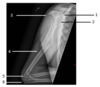

Identify structure 3: A - Humeral head B - Scapular body C - Humeral epicondyles D - Acromion

D - Acromion In the image of the lateral humerus, the numbers correspond as follows: 1. Coracoid 2. Humeral head (A) 3. Acromion (D) 4. Humeral shaft 5. Humeral epicondyles (C) 6. Olecranon